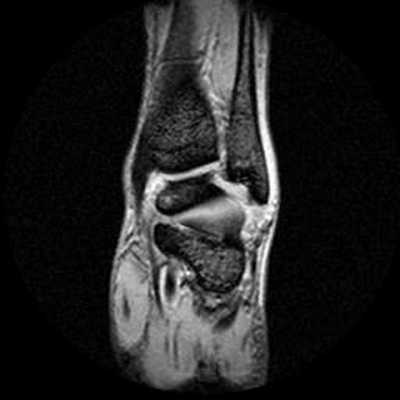

Что показывает МРТ голеностопного сустава

Какие заболевания покажет МРТ голеностопного сустава?

Но самым точным диагностическим методом является МРТ. При этом на снимках можно выявить изменения в структуре тканей менее 1 мм. Поэтому любая патология на МРТ будет видна намного раньше, чем при других методах исследования. А это большое преимущество в лечении, ведь чем раньше начать его, тем оно эффективнее. Иногда на ранней стадии можно обойтись без хирургического лечения. В случаях выявления опухолей шансы излечиться намного выше, при этом методы будут более щадящими, меньше объем оперативного вмешательства.

Поэтому МРТ широко используют в ортопедии и травматологии, онкологии. Вот, что показывает МРТ голеностопа: